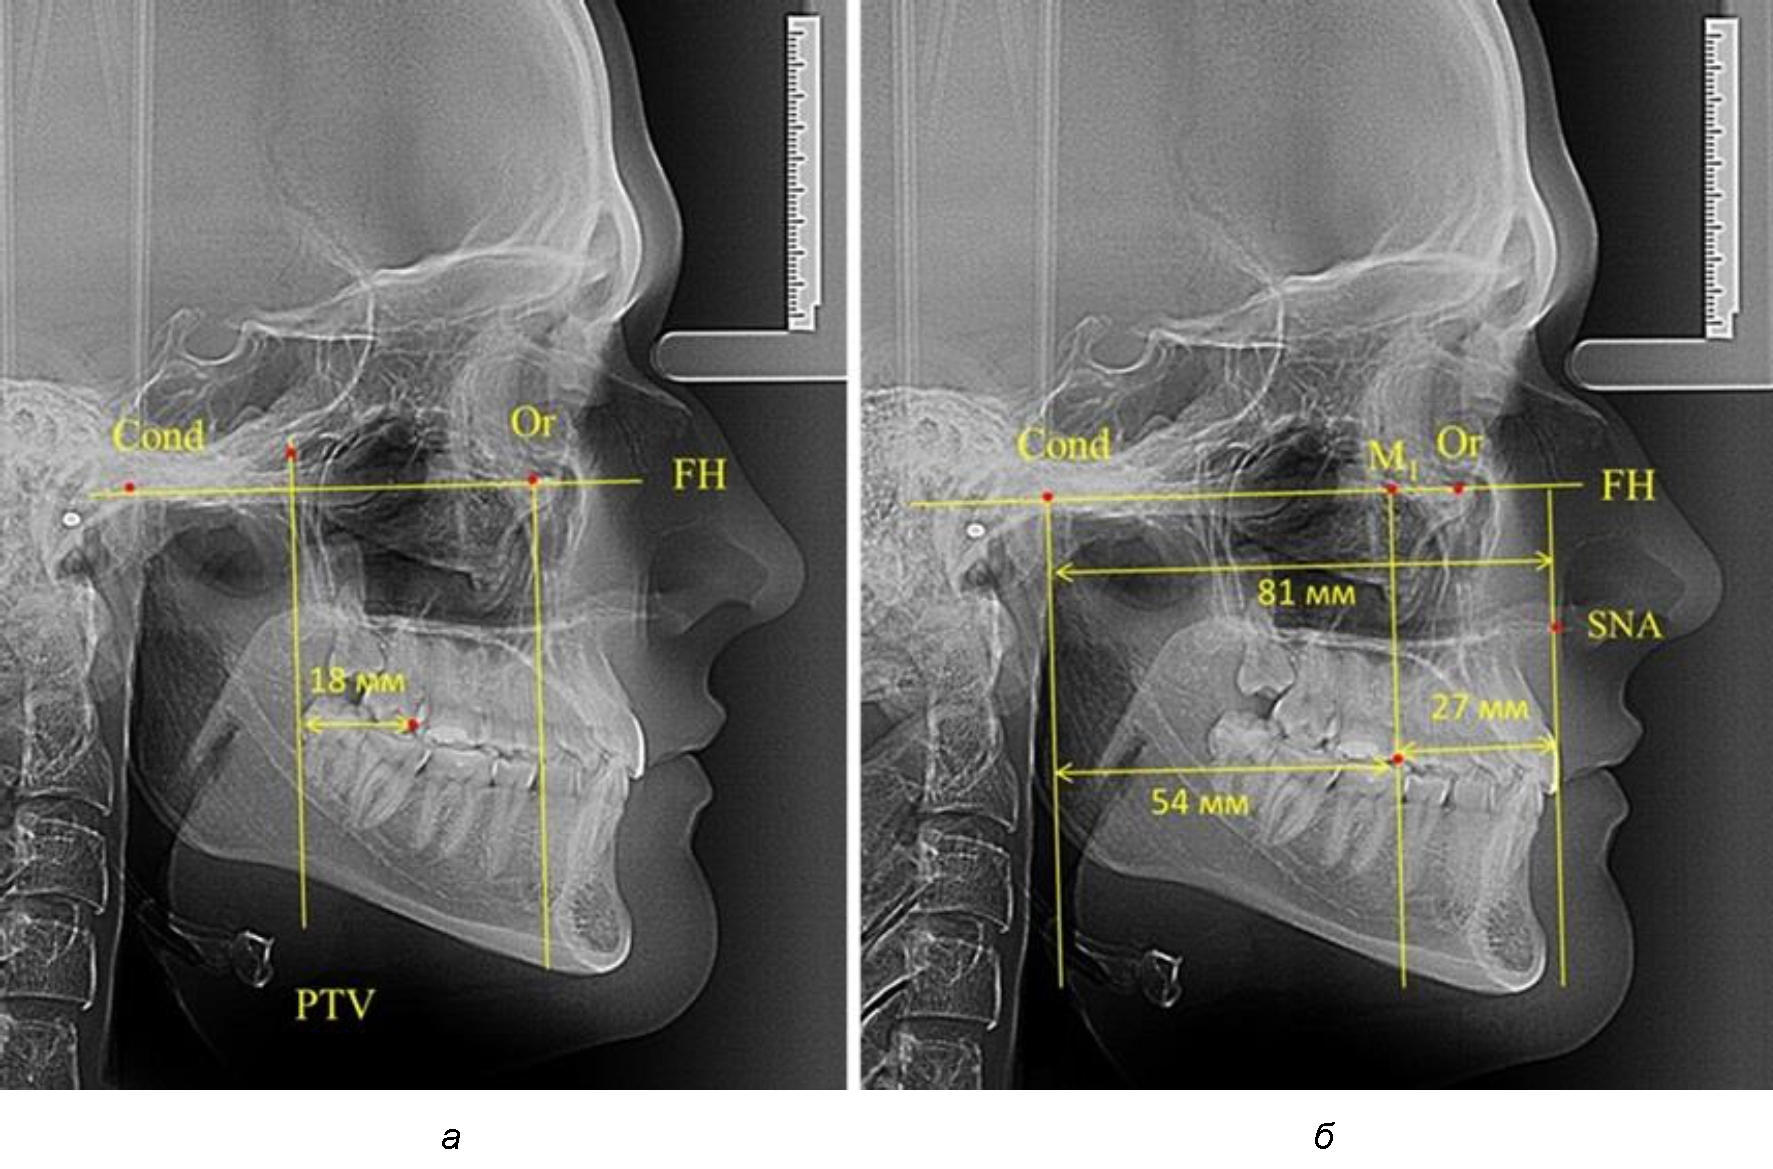

Рис. 3. Особенности положения первых моляров по R. E. McDonald (а) и по предложенному методу (б) при увеличенном молярно-крыловидном расстоянии

В то же время при увеличенном расстоянии от крыловидной вертикальной плоскости PTV до дистальной поверхности верхнего первого постоянного моляра, равное 23 мм, сагиттальный размер гнатического отдела составил 92 мм. При этом отношение кондилярно-спинального расстояния к кондилярно-молярному размеру (30,5), так же, как и при малых размерах, было близким к коэффициенту 1,5, что представлено на рис. 3.